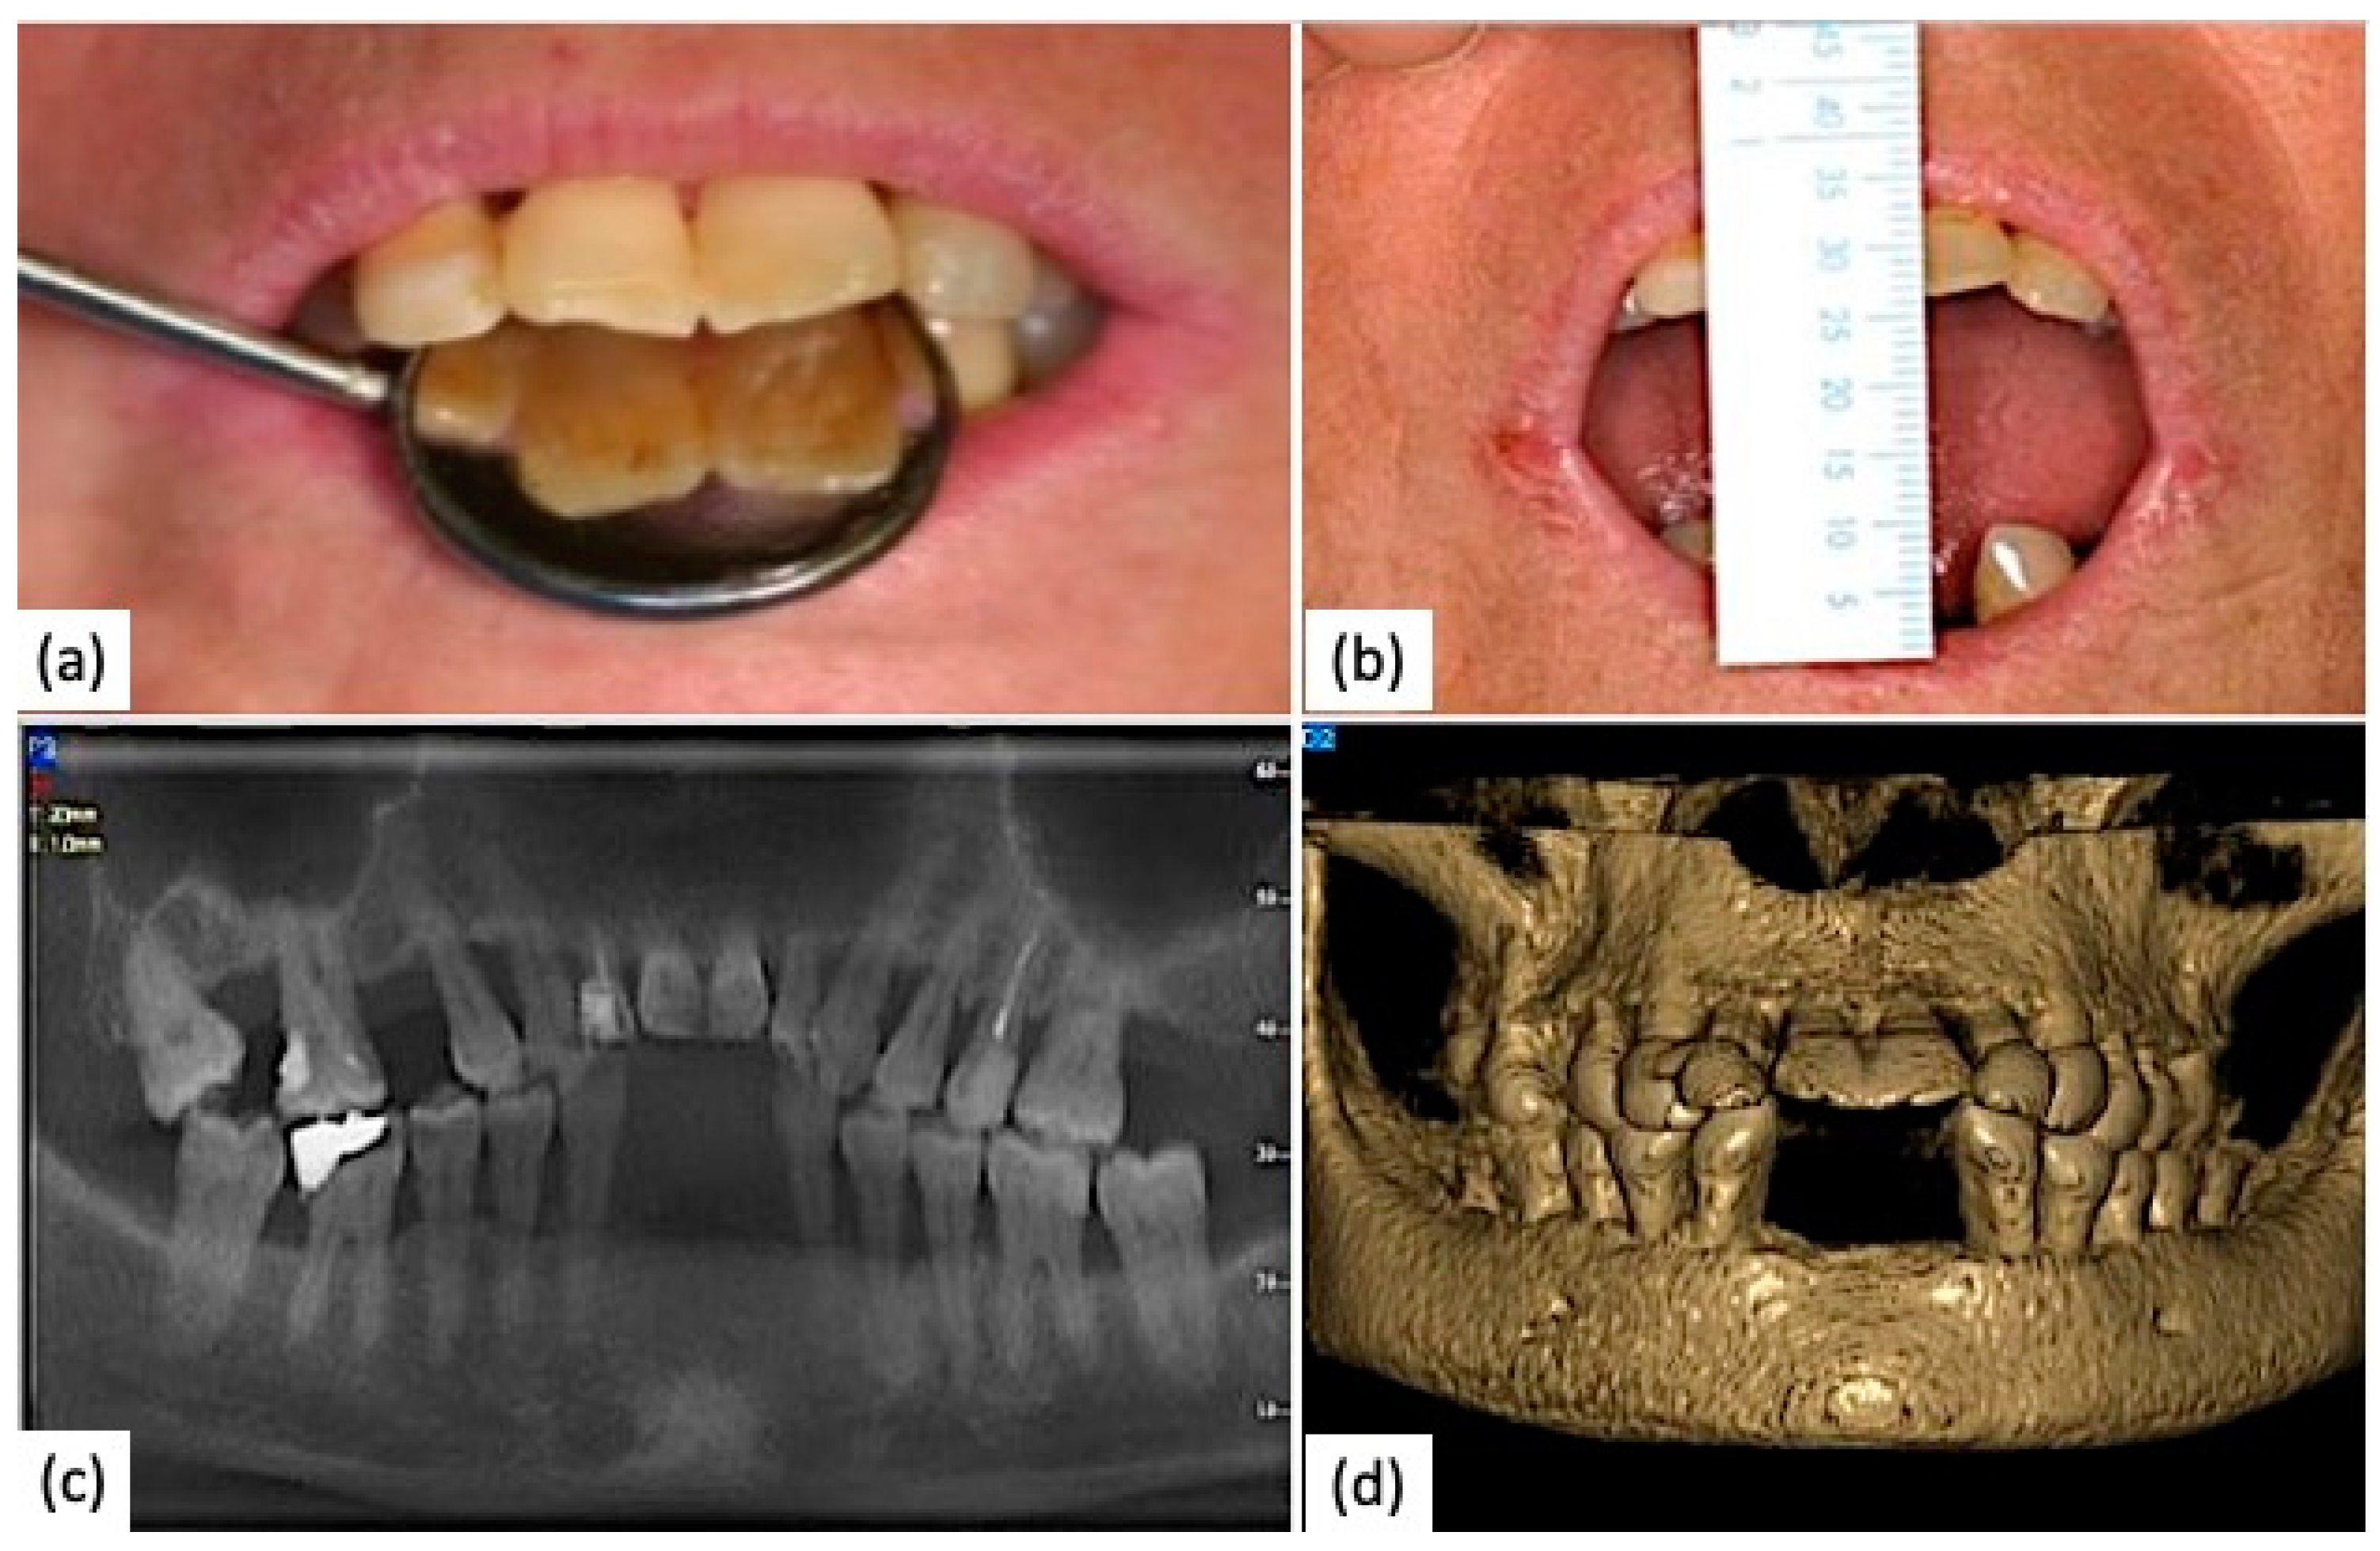

6. Clinical Case